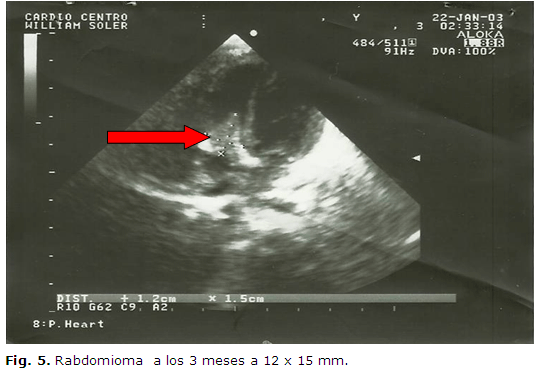

Ecocardiograma: (Figura 4)

Ecocardiogramas

evolutivos, a los 6 y a los 10 días de nacido, al mes y a los dos meses

de vida, sin cambios significativos, a los 3 meses había disminuido a 12

x

En el ecocardiograma realizado, al cuarto mes no se observa imagen tumoral intracardíaca, lo cual se confirma nuevamente a los 6 meses de vida.